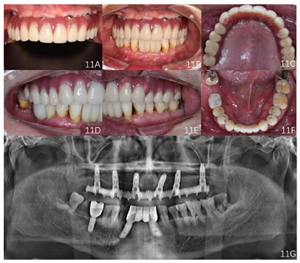

面像;G:戴牙后曲面断层片随访及转归:种植体支持式全牙列固定义齿修复后12个月复查:修复体完整稳固,表面及组织面清洁,复合基台周围软组织健康,发音清晰,正中及侧方咬合关系稳定(图11)。曲面体层片示种植体周围无透射影像。

面像;D:右侧咬合像;E:左侧咬合像;F:下颌

面像G:曲面体层片

面像G:曲面体层片下颌自然牙牙周专科检查未探及牙周出血及≥3 mm的牙周袋,牙龈色形质正常。详见牙周大表(图12)。